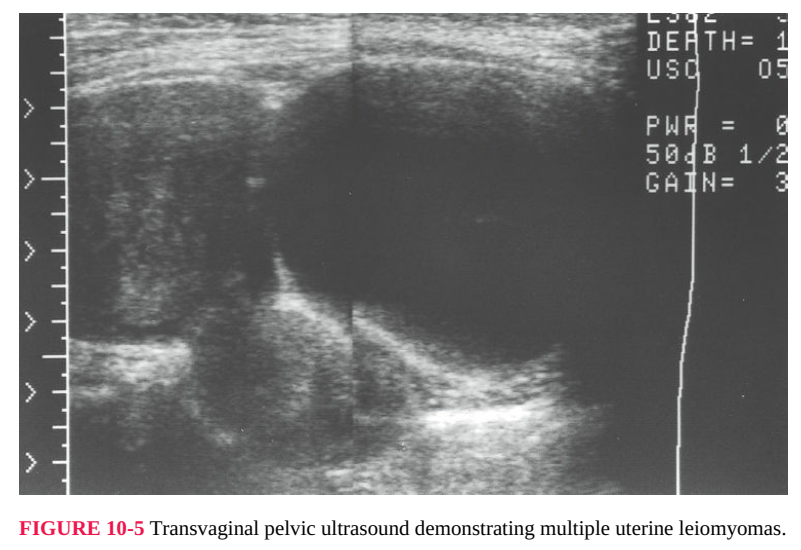

whether solid or cystic or mixed echogenicity. Diagnosis of uterine leiomyomas

usually is based on the characteristic finding of an irregularly enlarged uterus. The

size and location of the usually multiple leiomyomas can be confirmed and

documented with pelvic ultrasonography (Fig. 10-5). If the examination is

FIGURE 10-5 Transvaginal pelvic ultrasound demonstrating multiple uterine leiomyomas.